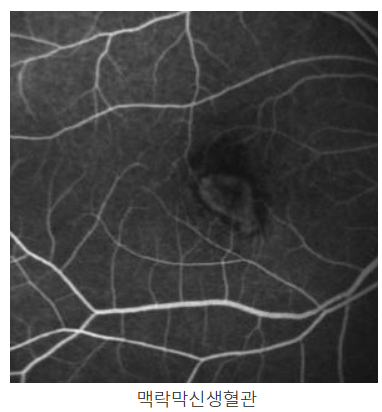

- 안과 검사: 망막의 상태를 체크하고, 황반의 염증 여부를 확인하는 것이 중요합니다. **광학 단층 촬영(OCT)**과 망막 검사 등을 통해 망막의 변화를 모니터링합니다.